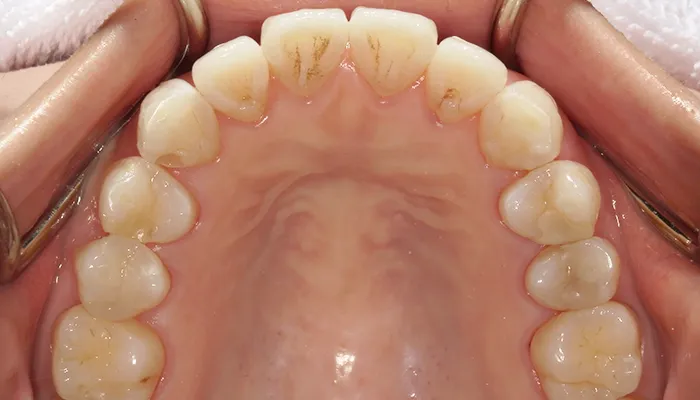

治療後の口腔内写真

術後の口腔内写真

右下5番のインプラントは良好に骨結合し、自然な形態と色調の補綴物を装着しました。

インビザライン矯正により歯列が整い、清掃性・咬合バランスともに改善しました。

ホワイトニングにより歯全体の色調が明るくなり、笑顔の印象が大きく改善しました。

患者様は審美性・機能性ともに大変満足していらっしゃいました。